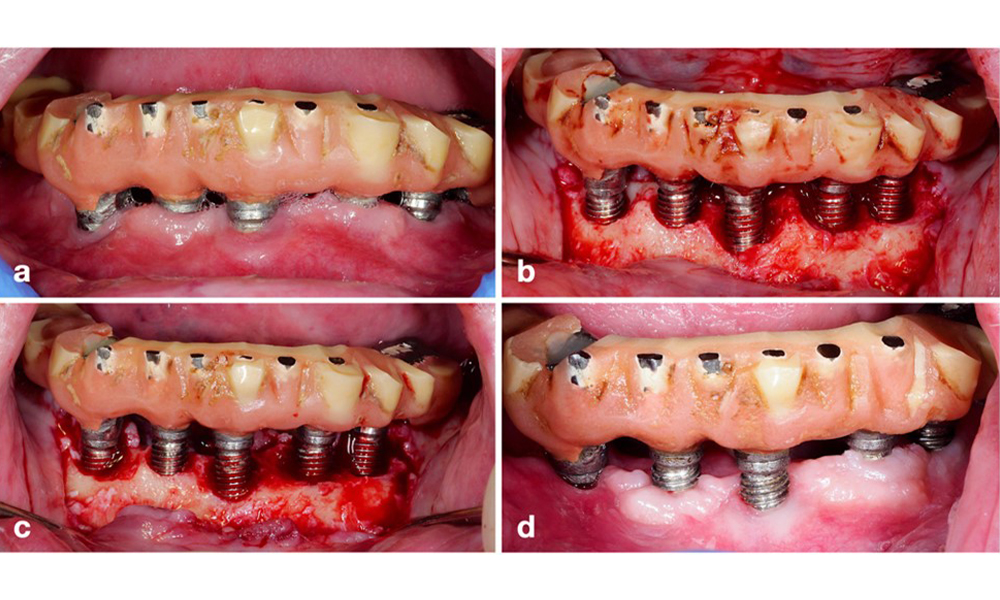

Management of peri-implantitis at implants judged as treatable consists of a non-surgical phase, which is often followed by surgical intervention. For the non-surgical approach, similar measures as those applied for the treatment of peri-implant mucositis are used; based on laboratory experiments air-polishing devices with a subgingival nozzle appear to provide certain advantages in terms of biofilm removal, compared to hand- or ultrasonic instruments (Herrera et al. 2023; Moharrami et al. 2019; Ronay et al. 2017) (figure 9).